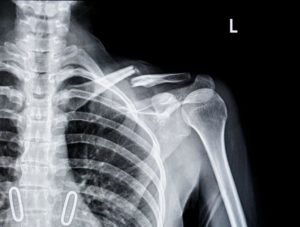

Zlomenina klíční kosti

Nejčastějším cyklistickým úrazem ramenního pletence je zlomenina klíční kosti po pádu z kola. Jistě jste někdy zaregistrovali zprávu o fraktuře klíčku na Tour de France, v cyklistice jsou takřka na denním pořádku. Skoro by se dalo říct, že řádný cyklista se pozná podle zlomené klíční kosti a jizev na bocích v oblasti hlavice stehenní kosti. Alespoň já je takto v ordinaci vždy odhalím. Cyklista má při pádu tendenci ho zmírnit natažením ruky a při nárazu praskne nejslabší článek řetězce, tedy klíční kost. Po pádu to vypadá typicky tak, že cítíte bolest v rameni a nemůžete zvednout ruku. V takovém případě okamžitě vyhledejte lékařskou pomoc. Nejsme Štybarové ani Kreuzigerové a nejsme na Tour de France, nepotřebujeme dokončit etapu, ale být schopni zdravě a s mírou sportovat celý život. Proto po pádu z kola není vhodná chvíle na hrdinství, ale na návštěvu nemocnice. Zlomenina klíční kosti se řeší buď konzervativně, nebo operativně podle konkrétního stavu a rekonvalescence trvá nejčastěji 4 až 8 týdnů. Návrat do předchozího stavu je individuální a závisí mimo jiné i na tom, zda jste včas šli k lékaři. Poté, co kosti srostou, doporučuji návštěvu fyzioterapeuta, který pomůže s funkčním zapojením pletence ramenního a návratem ztraceného rozsahu pohybu.

Zlomenina levé klíční kosti